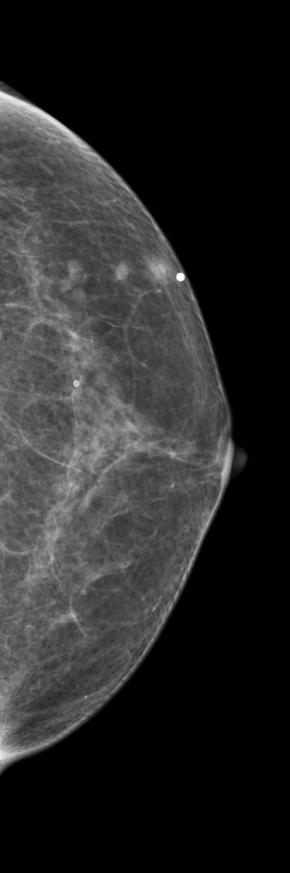

[355,Breast] 61/F,A palpable mass in the left breast

Breast

US,Etc,

What is your diagnosis?